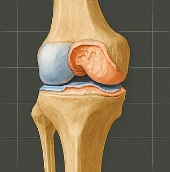

무릎 연골은 대퇴골(허벅지뼈)과 경골(정강이뼈) 사이에 존재하며, 충격을 흡수하고 관절을 부드럽게 움직이게 도와줍니다. 연골이 마모되거나 찢어지면 관절 간 마찰이 심해지고, 염증과 통증이 발생합니다. 대표적인 형태는 다음과 같습니다.

- 반월상연골 손상: 무릎 중앙의 C자 형태 연골이 찢어짐